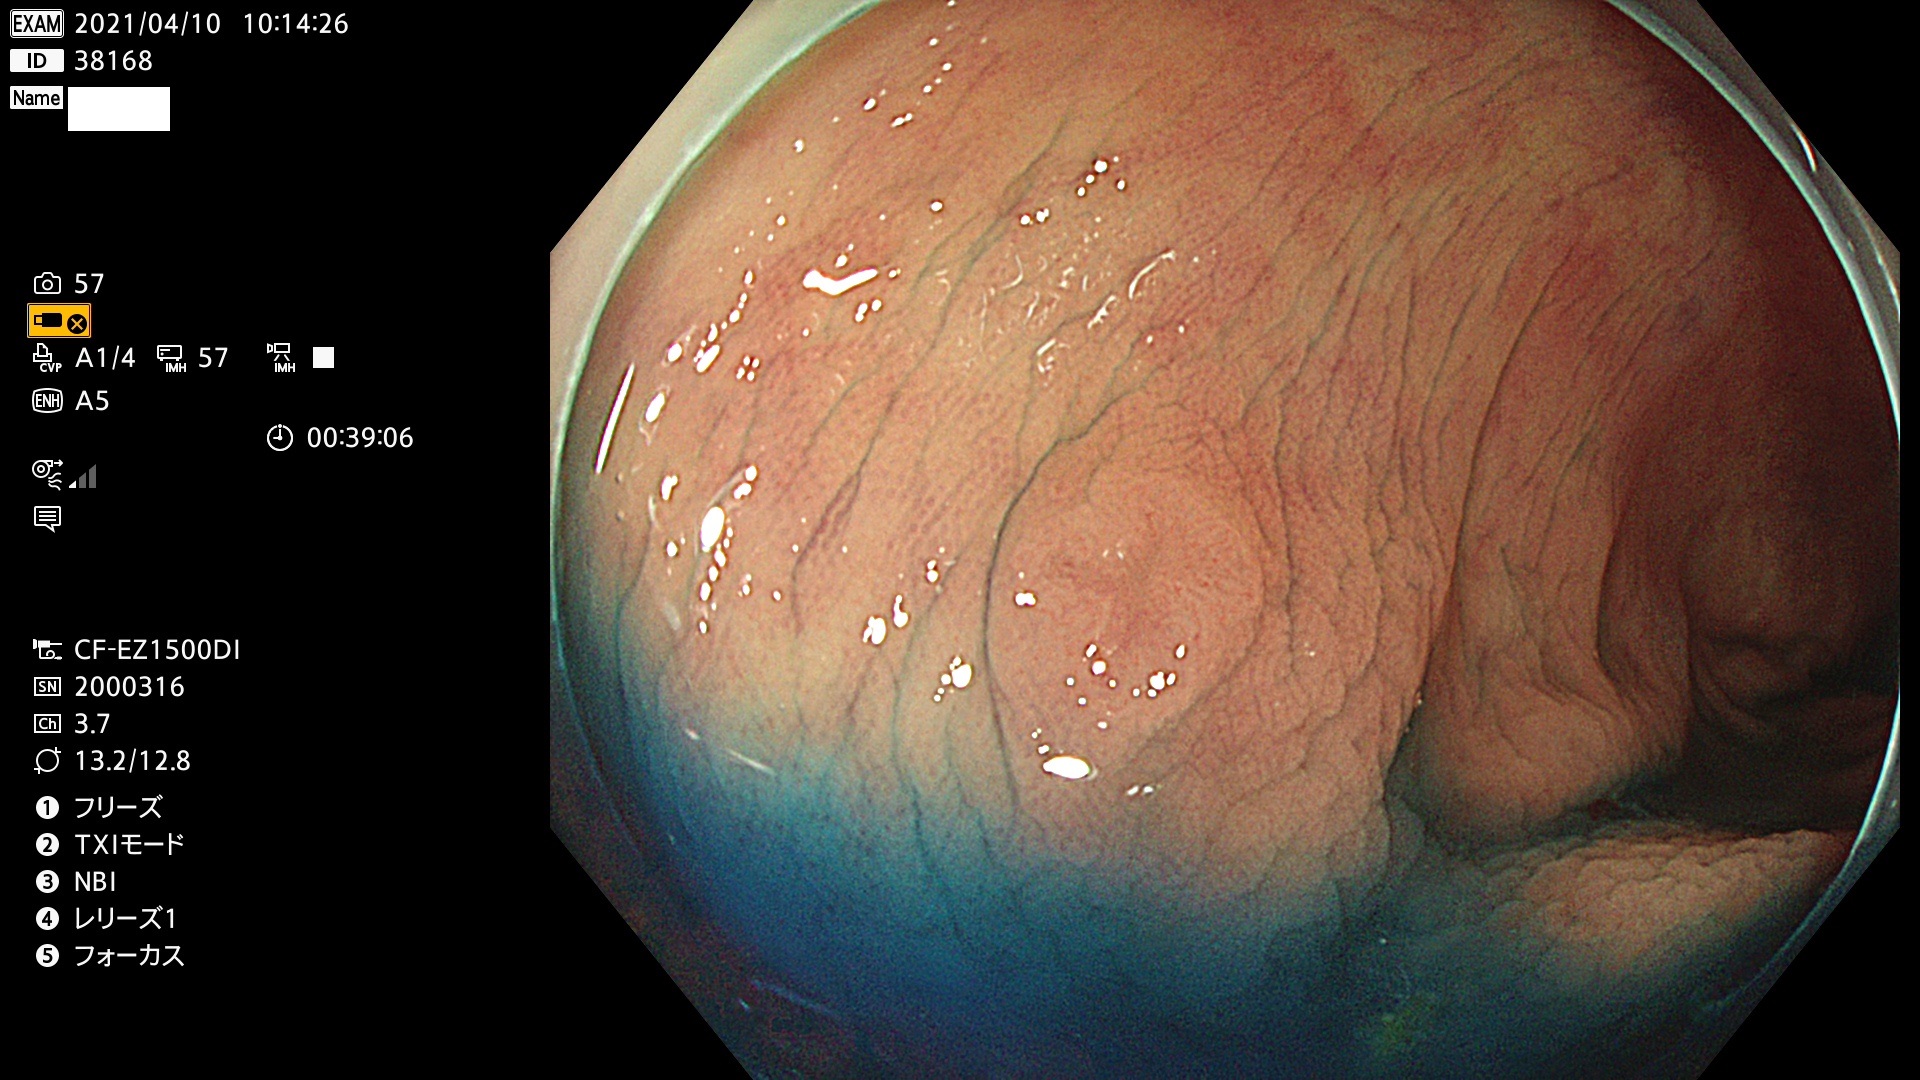

腺腫発見率 72 % (カルテ番号 38100〜38199の100名の方の検査結果で集計)大腸癌検診最新情報

以下のカルテ番号の方に腺腫(Adenoma,Group3〜5)が見つかりました(集計法)

38101 38103 38104 38106 38107 38108 38109 38110 38111 38112 38113 38114 38115 38117 38118 38122 38123 38124 38125 38126 38127 38128 38130 38131 38132 38135 38137 38138 38140 38141 38142(SSAPのみ) 38143 38144 38145 38146 38147 38148 38149 38150 38151 38152 38153 38154 38157 38158 38160 38161 38162 38164 38165 38166 38167 38168 38169 38172 38176 38177 38178 38181 38182 38183 38184 38187 38189 38190 38191 38192 38193 38194 38195 38196(SSAPのみ) 38198

発見困難で危険性の高い平坦型病変(上記100名より抽出) ![]()